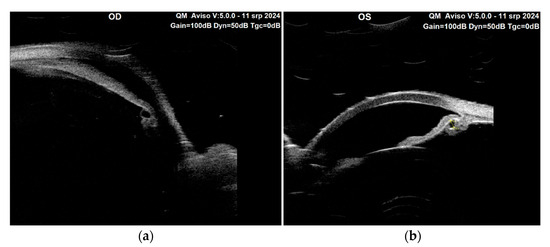

Figure 4. Ultrasound biomicroscopy (UBM) with 50 MHz transducer, (Quantel Aviso, Topcon, Tokyo, Japan) provided crucial insights into the structural characteristics of the anterior segment in both eyes, as illustrated in Figure 4. The UBM examination revealed the presence of cystic formations within and around the ciliary body in the left eye, which is often indicative of various pathologies including ciliary body cysts. Primary ciliary body cysts are benign, fluid-filled cavities from the iris and ciliary body, often found incidentally during eye examinations [4,5,6]. However, they can pose risks such as angle-closure glaucoma if they cause the anterior chamber angle to exceed 180 degrees or if multiple cysts displace the iris forward, resembling pseudoplateau iris [5]. Interestingly, cystic areas were also unexpectedly detected in the right eye, suggesting that there may be a bilateral component to the underlying pathology, despite the differences noted in angle status between the two eyes. In addition to the identification of these cysts, the UBM findings highlighted an axially wide anterior chamber in the left eye, which is typical of reverse pupillary block. This reduced chamber depth can be associated with several issues, including an increased risk of angle closure and elevated IOP. Furthermore, the examination confirmed the presence of a reverse pupillary block in the left eye. Figure 4 shows the performance of the UBM on the right eye (a) and the left eye (b) with ciliary body cysts pushing the peripheral iris and causing angle closure with an associated reverse pupillary block in the left eye. One possible bias in the execution of the UBM arises from the supine position in which it was conducted. This position may cause a posterior displacement of the lens, resulting in a deeper anterior chamber. It is crucial to take this positional change into account, as it could affect the interpretation of the images.